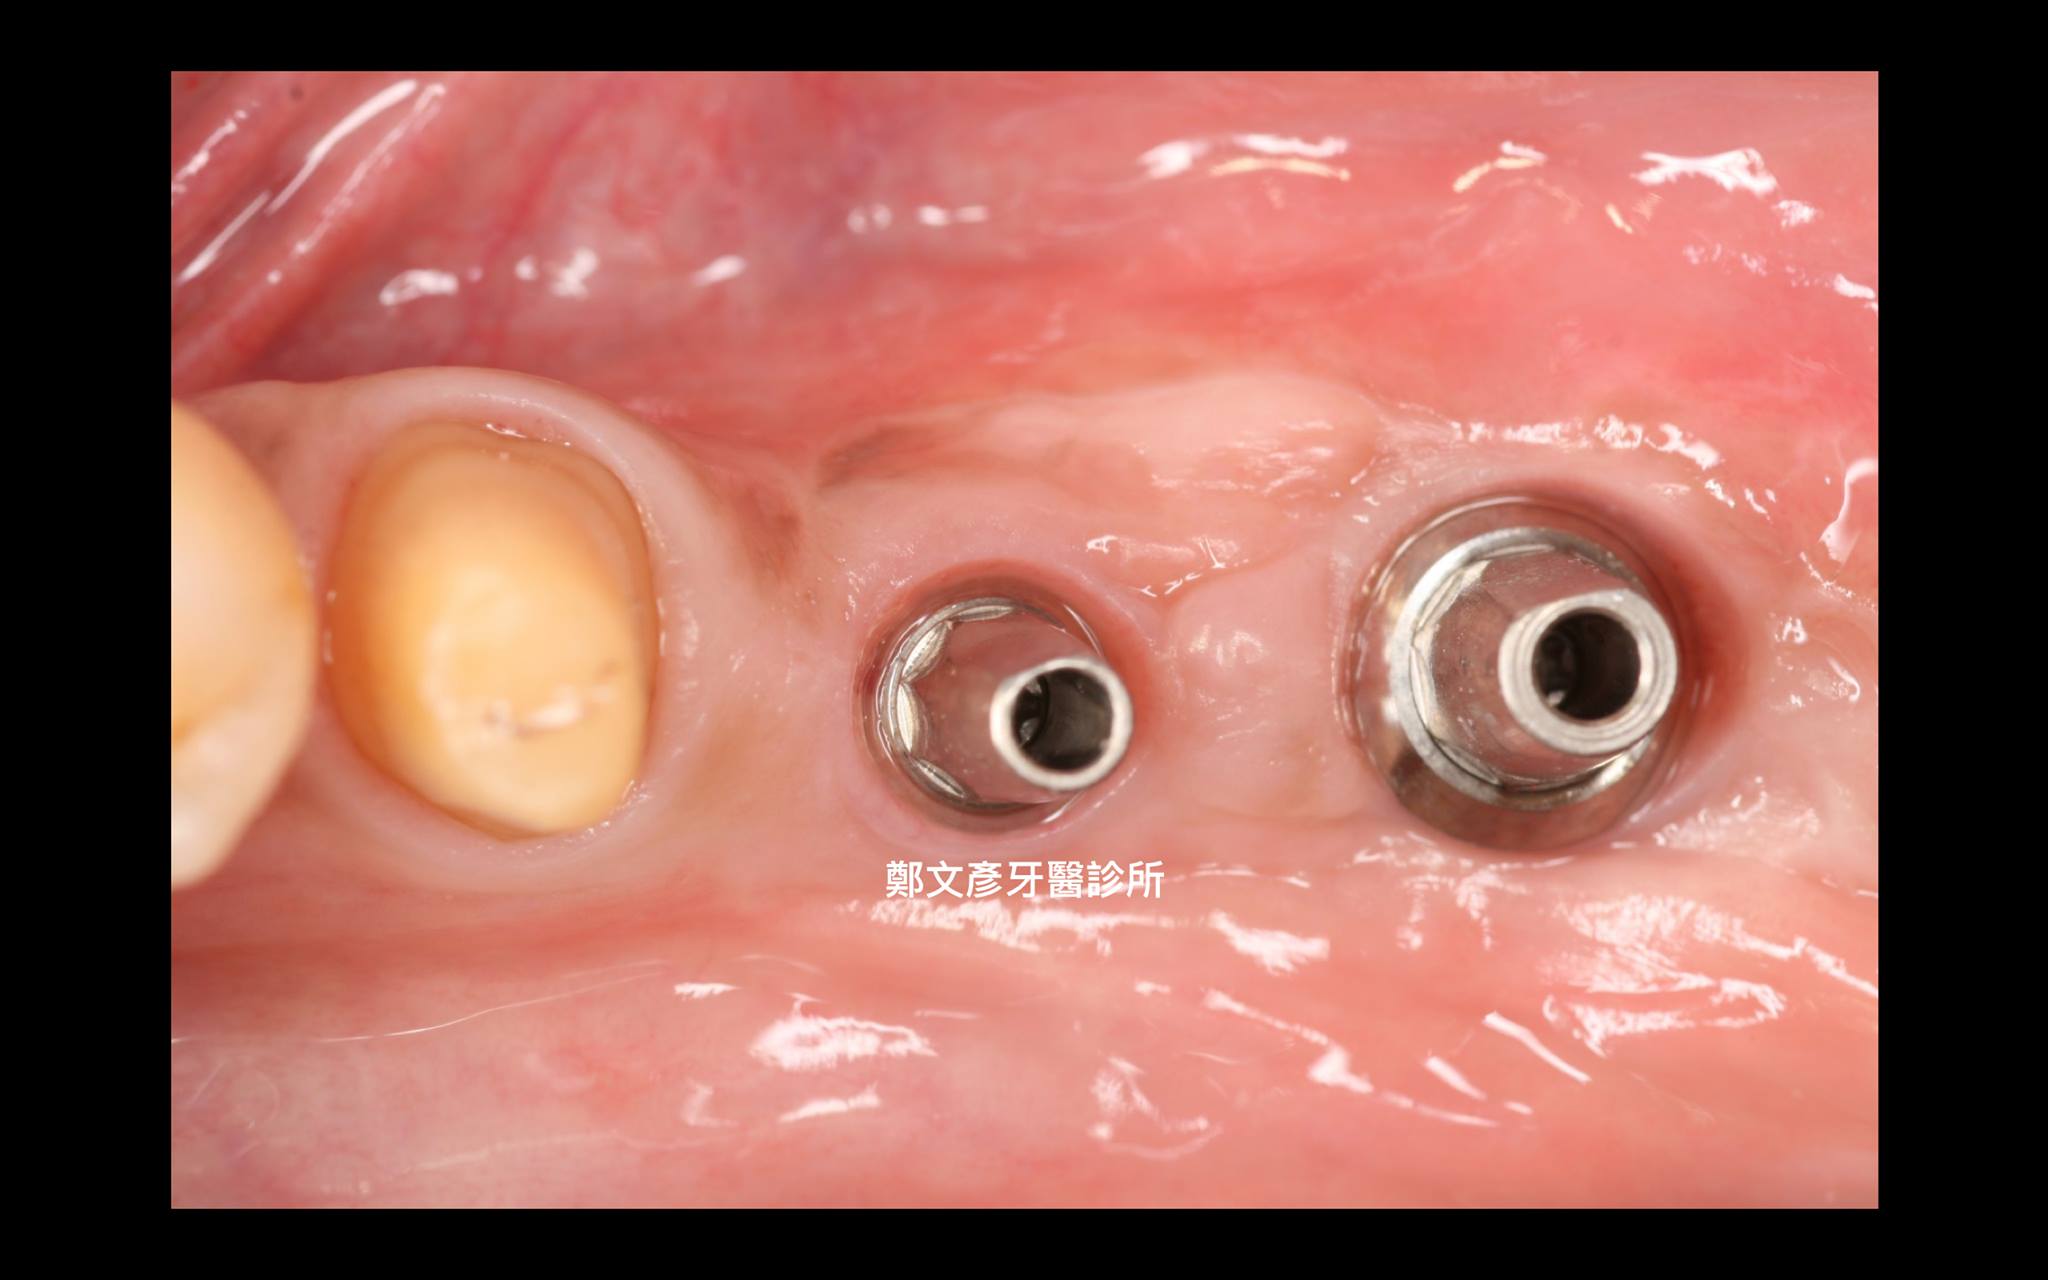

植牙美學(後牙區)

植牙美學